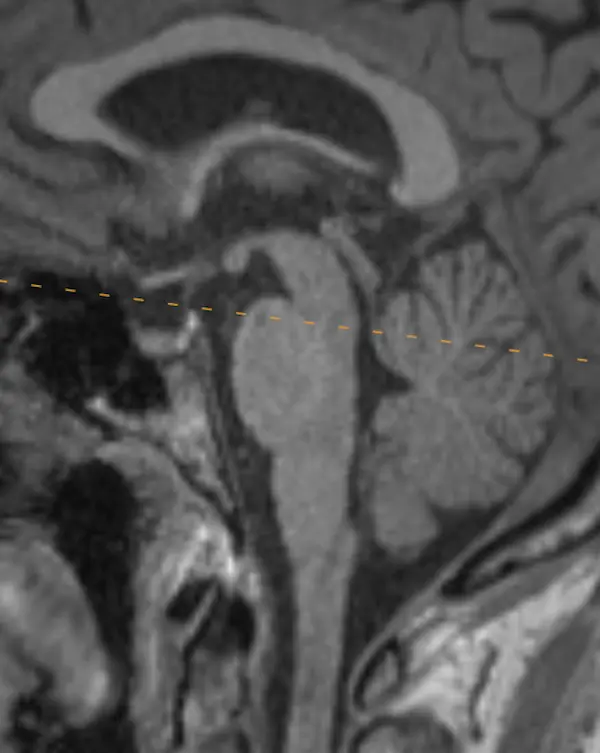

Note that axial planes in brain imaging are not perfectly perpendicular to the brainstem, they are instead created by drawing a line through the anterior commissure (AC) and posterior commissure (PC); the so-called AC-PC line. Keep this in mind when correlating the appearance of structures in the axial plane to sagittal.

The brainstem, outlined in a white dotted line, is divided into the midbrain, pons, and medulla. Each segment has a characteristic appearance that is easiest to recognize in the sagittal plane.

Notice the beak-shaped anterior margin of the midbrain and the cerebrospinal fluid (CSF) space underneath it.

The pons has a bulbous contour anteriorly and a triangular shaped CSF space posterior to it.

The medulla is thin, gradually blends in appearance with the cervical spinal cord, and has a small CSF channel posterior to it.